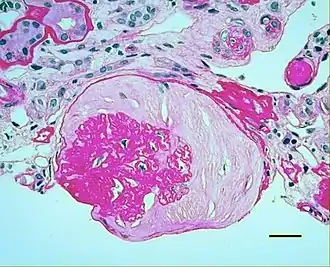

In benign nephrosclerosis, the changes occurring are gradual and progressive, however, there can be sufficient kidney reserve capacity to maintain adequate kidney function for many years.[10] The large renal arteries exhibit intimal thickening, medial hypertrophy, duplication of the elastic layer. The changes in small arterioles include hyaline arteriolosclerosis (deposition of hyaline, collagenous material), which causes glomerular collapse (wrinkling and thickening of capillary basement membranes and collapse of capillary lumen) and solidification (glomeruli exhibit sclerosis and increase in mesangial matrix). The degree of scarring correlates with the degree of glomerular filtration deficit.

Light micrograph showing hypertensive glomerular lesion of hypertensive nephropathy: global glomerular collapse and filling of Bowman's space with a lightly staining collagenous material. -